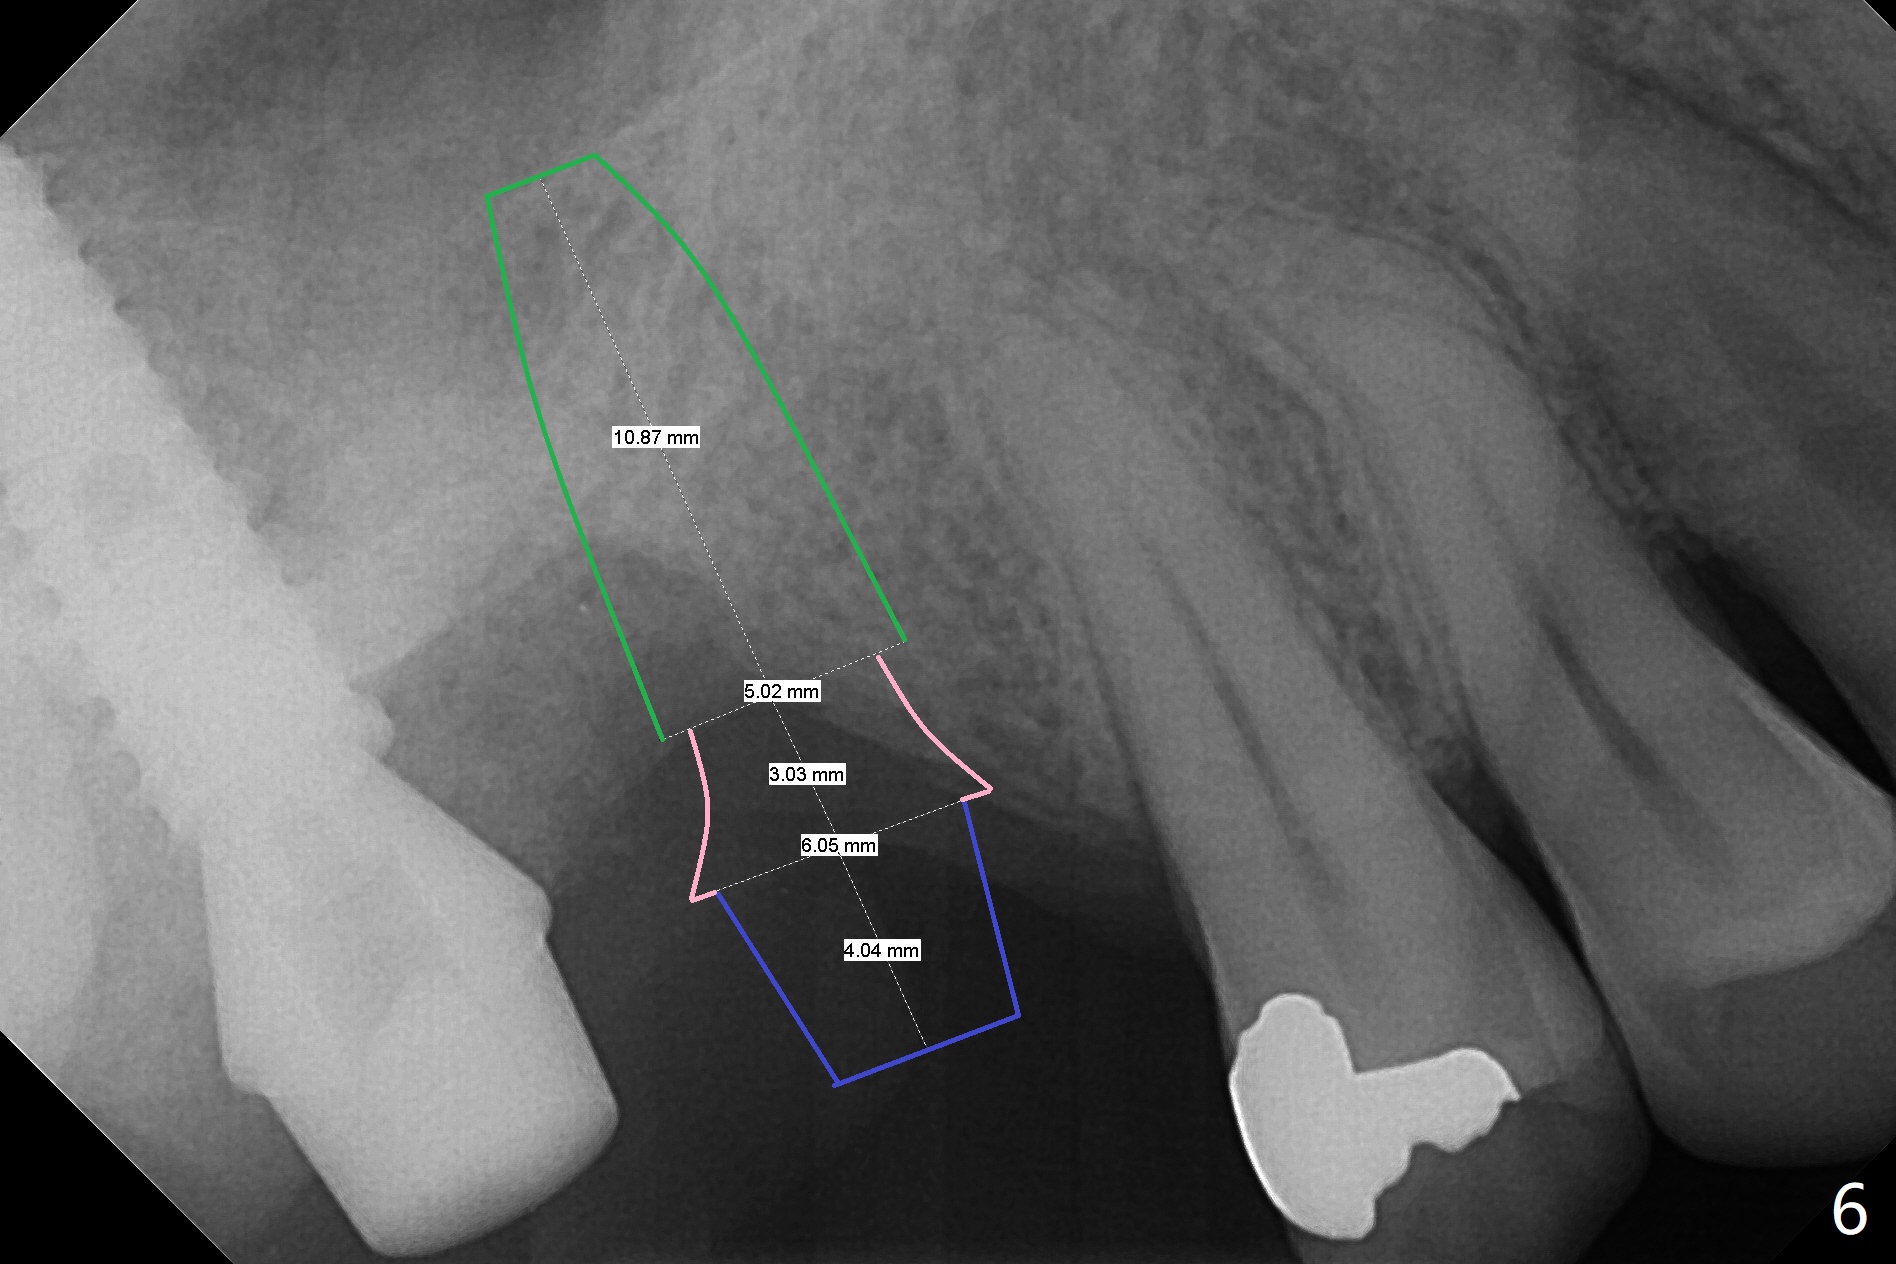

It is difficult to use hard tissue landmark (drill stopper) to make osteotomy in the fresh extraction socket because of socket irregularity and hemorrhage. Once osteotomy is initiated, depth is more reliably controlled with soft tissue landmark (such as gingival margin). This happens in today's case. Without CT information, the osteotomy is established in the buccal slope of the septum of the tooth #2 (after extraction) by using alternatively Magic Sinus Lifter and 4.8 mm Magic Drill (MD). Finally the sinus floor (Fig.1 red dashed line) is lifted after the MD reaches ~16 mm counting from the gingival margin, consistent with preop panoramic X-ray and intraop PA measurement. The 4.5x11 mm dummy implant is close to the impacted 3rd molar (1). Following use of Lindamann bur to move the osteotomy mesially, a 5x9 mm dummy implant is placed away from the 3rd molar (Fig.2 (3: residual root of the 1st molar)). The latter is intentionally not removed in order to maintain osteotomy integrity. A 5x13 mm IBS implant is placed with >50 Ncm; a 6.5x4(4) mm abutment is hand tightened (Fig.3). The remaining large socket is filled with Vera Graft (Fig.4 *). Two months postop, the abutment changes to 6.5x5.7(2) mm without provisional (Fig.5). Nearly 3 months postop, the patient will return for #3 residual root extraction and implant placement with incision (Fig.6). Osteotomy will be initiated in a slope. Prepare surgical round bur for flattening. After placement of a healing abutment, periodontal dressing is to be applied. Take photos to show gingival adaptation to the new abutment without implant exposure at #2.